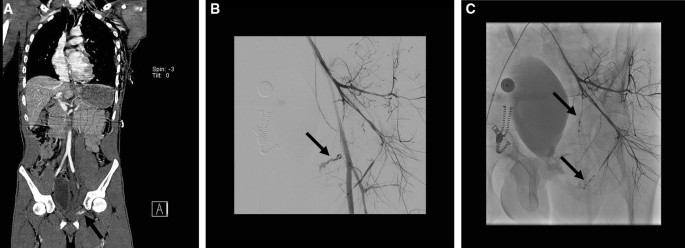

Depending on the hemodynamic status of the patient and the time pressure, embolization is best performed selectively or non-selectively. Time permitting, selective embolization is preferred when there are only one or a few focal bleeding vessels (Fig. 2), when hemodynamics are stable. Superselective embolization, which often requires use of 2–3-Fr micro-catheters through a coaxial system, is technically more demanding and therefore time-consuming and is associated with a higher incidence of recurrent pelvic arterial hemorrhage [13]. Non-selective embolization (Fig. 3) is less time-consuming and can be performed using standard 4 or 5 Fr. catheters is preferred in hemodynamically unstable patients with ongoing hemorrhage. Non-selective unilateral embolization of the whole IIA or of the entire posterior or anterior division of the IIA can safely be performed in an emergency or if multiple vascular injuries or diffuse hemorrhage is found, which may occur in up to 40% of cases [10, 34]. Non-selective bilateral embolization of the entire IIA is a last resort for severe bleeding, but a widely accepted method without significant complications [40]. Superselective bilateral distal embolization is best avoided, as collateral blood supply from the contralateral IIA would be compromised, leading to an increased risk of tissue necrosis. Cessation of contrast extravasation from the affected vessel during the procedure is proof of technical success.

Fig. 2

figure 2

A coronal whole-body CECT of a hemodynamically stable trauma patient with a fracture of the left superior pubic ramus with pelvic hematoma and a contrast blush (black arrow). B Subsequent selective angiogram of the left internal iliac artery (with retrograde filling of the external iliac artery) shows constricted vessels and a focal contrast extravasation “blush” (black arrow) suitable for superselective embolization with coils and C selective angiogram of the left internal iliac artery after selective embolization with coils (black arrows)